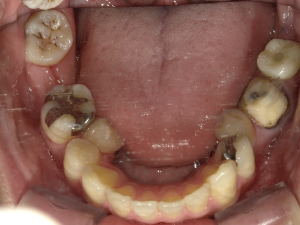

30代 女性 インプラント治療(鎮静療法)

| 主訴 | 口腔内かなり状態悪く、これから先しっかり噛んで食事ができるようにインプラントを入れたい。 |

| 部位 | 左上3,5,7、右下5 |

| 治療期間 | 約11ヶ月 |

| 費用 | ¥2,145,000(税込) |